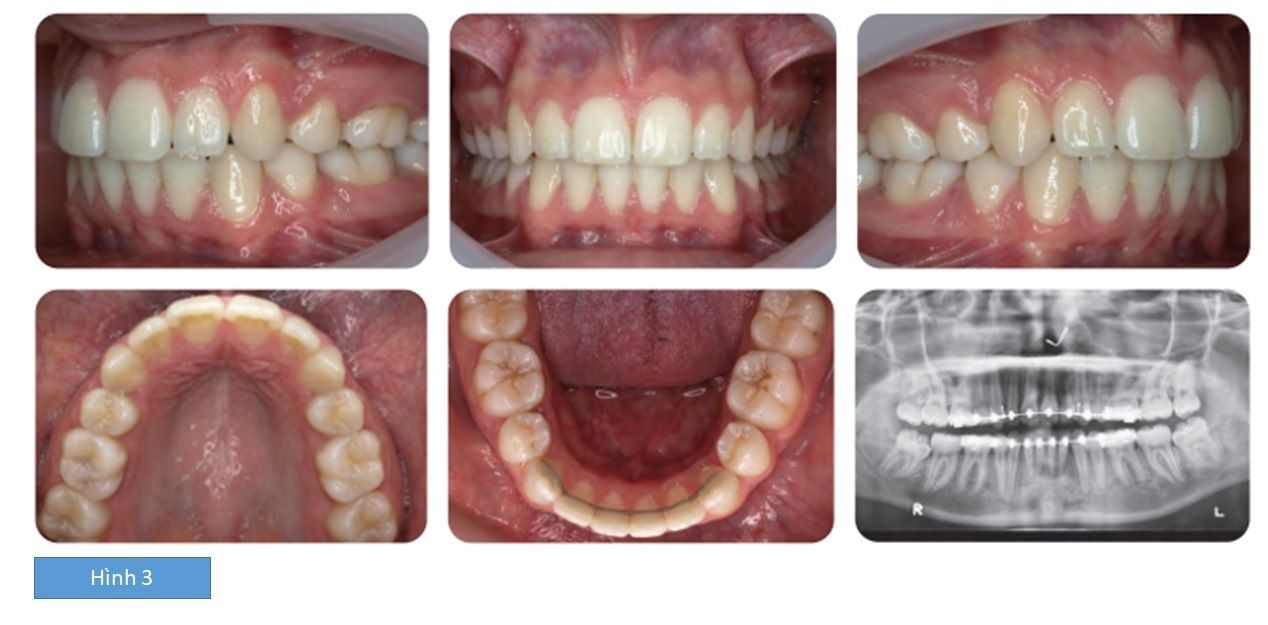

Kết quả: bệnh nhân đạt được tương quan răng loại I, độ cắn chìa giảm đáng kể và răng thẳng hàng, đều đặn, hết chen chúc. (hình 3)